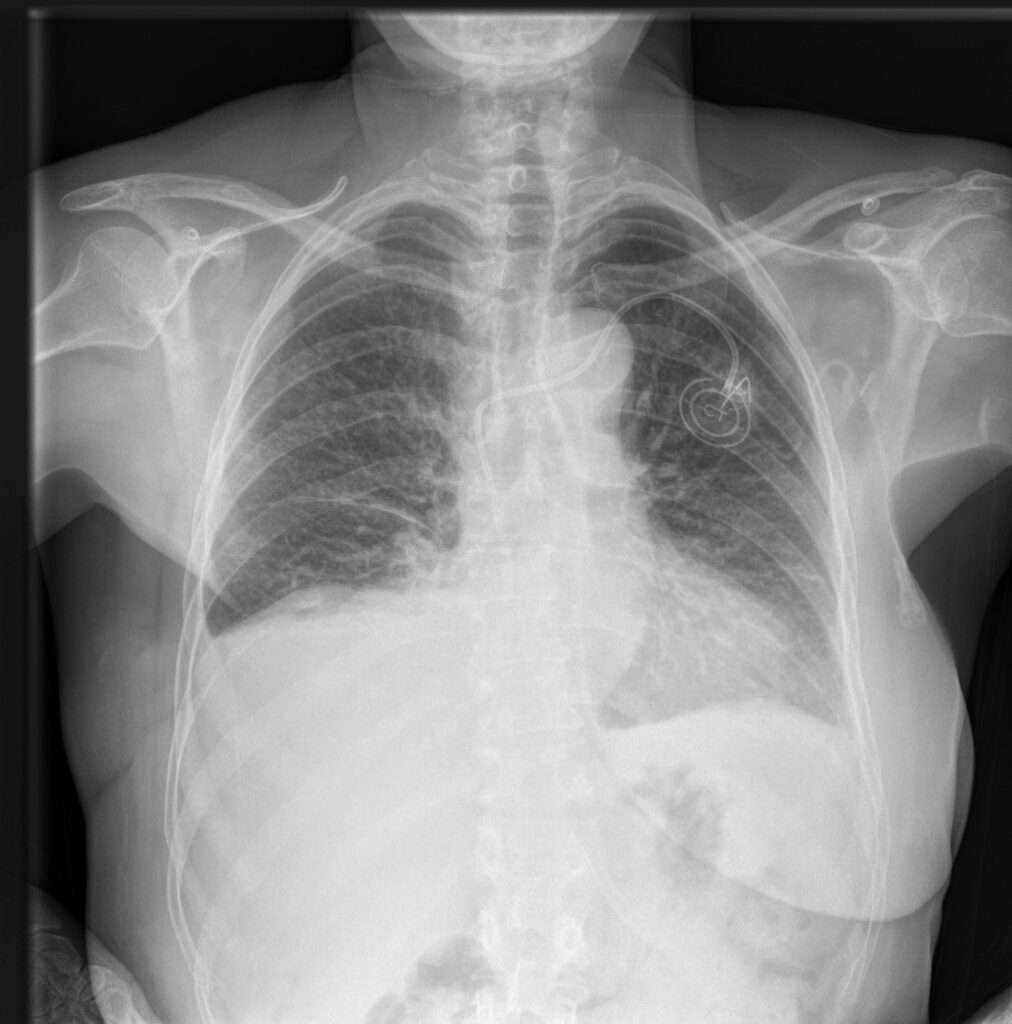

Hvor traditionel billedbehandling justerer kontrasten globalt, arbejder MUSICA3 på et mikroniveau. Hvert billede opdeles i lag – hvert lag behandles separat – og resultatet er, at du ser detaljer, der ellers ville forsvinde i overgangszonerne mellem lyst og mørkt væv.

Det gælder særligt i de klinisk vanskelige områder.

- Balanceret fremstilling af blødt væv og overlappende knogler

- Skarpe detaljer i mediastinum og abdominalorganer

Musica3 Chest+

MUSICA®3 Chest+ kompenserer for scatter og leverer billedkvalitet, der svarer til eksponering med fysisk anti-scatter grid – ved 1,6 gange lavere dosis.

- Reduceret dosis og ingen risiko for grid-artefakter

- Markant bedre kontrast i lungefelter og mediastinum uden grid